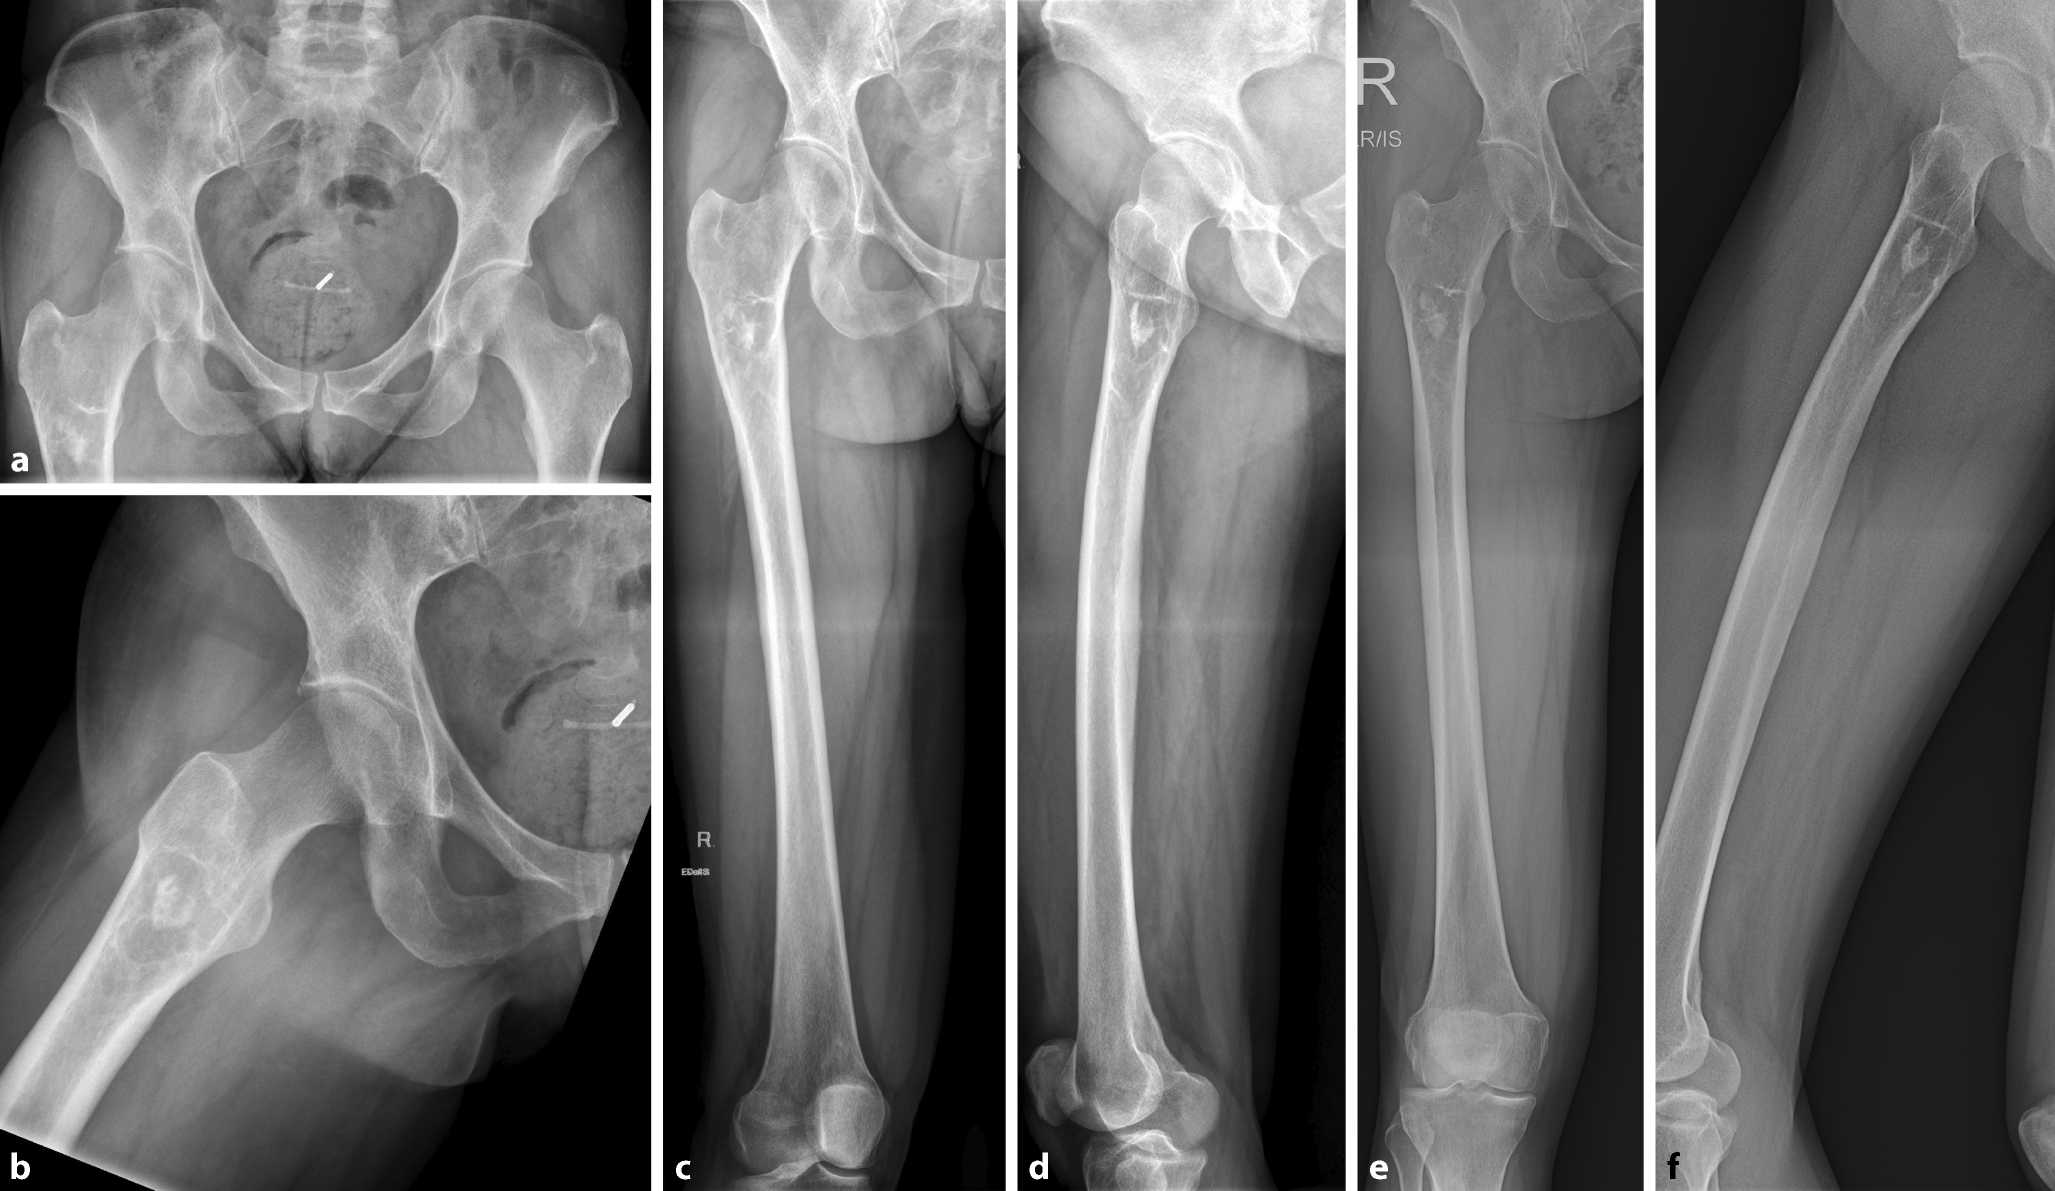

Bei einer 50-jährigen Patientin wurden bei länger andauernden ziehenden Schmerzen in der unteren Lendenwirbelsäule, ausstrahlend in den rechten proximalen Oberschenkel, Röntgenbilder des Beckens und der rechten Hüfte angefertigt (Abb. 3a, b). An der mitabgebildeten unteren Lendenwirbelsäule zeigten sich inzipiente degenerative Veränderungen. Auffallend war am proximalen Femur rechts eine zentral verkalkte, gut randsklerosierte, „milchglasartig“ imponierende Läsion ohne Periostreaktion oder Kortikalisdestruktion.

Abb. 3

Röntgenbilder einer 50-jährigen Patientin über einen Zeitraum von 4 Jahren. In der Initialbildgebung (a Beckenübersicht; b Hüfte rechts axial) zeigt sich eine zentral verkalkte, randsklerosierte Läsion mit „milchglasartiger“ Matrix ohne umgebende Periostreaktion oder Kortikalisdestruktion. Das nativradiologische Erscheinungsbild ist typisch für eine fibröse Dysplasie. In der Röntgenkontrolle nach einem (cd) und 4 Jahren (ef) kommt die Läsion unverändert zur Darstellung

Aufgrund des typischen radiologischen Erscheinungsbilds (siehe unten) wurde die Verdachtsdiagnose einer monoostotischen fibrösen Dysplasie (FD) gestellt. Es wurde eine bildgebende Verlaufskontrolle in jährlichen Abständen empfohlen, bei Auftreten von Beschwerden früher. Die ziehenden Schmerzen in den rechten Oberschenkel wurden auf degenerative Veränderungen der unteren Lendenwirbelsäule zurückgeführt. Diese besserten sich im Verlauf unter konservativer Therapie (Rückentraining, Schmerztherapie). Ein Jahr (Abb. 3c, d) bzw. 4 Jahre später (Abb. 3e, f) war die Patientin bezüglich des rechten Oberschenkels beschwerdefrei. Die Läsion im proximalen Femur rechts zeigte sich unverändert.